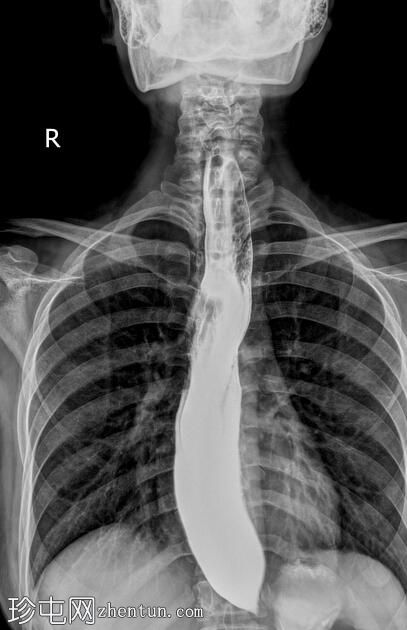

透视检查

正位

食管扩张,远端平滑狭窄并呈锥形(鸟嘴状),符合贲门失弛症的特征性表现

食管黏膜形态正常,无异常或溃疡

未见食管裂孔疝

钡餐检查显示食管扩张,远端狭窄并呈锥形,形成符合贲门失弛症特征的鸟嘴状外观。